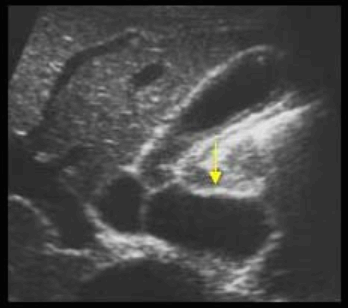

미리찌 증후군 (Mirizzi's syndrom) Mirizzi's syndrom 은 담낭경부, Hartmann's pouch 혹은 담낭관의 결석에 의해 총 간관(CHD)이 폐쇄되는 질환이다. 총 간관(CHD)이 협착되면서 상부담관은 확장되고 하부담관의 직경은 정상으로 나타난다. 증상은 폐쇄성 황달, 복부통증, 발열 등이 나타난다. 급성담낭염이 있으면서 담관폐쇄를 동반할 경우 의심해 볼 수 있다. 담낭절제술 후에 남아있는 담낭관의 결석이 총 간관(CHD)을 직접 누르거나 염증성 협착을 유발하기도 한다.

US finding

- 담낭관 또는 담낭 경부에 결석이 확인된다.

- 총간관(CHD) 또는 담낭관(cystic duct)의 확장소견이 보인다.

- 간내외 담관의 확장이 관찰된다.